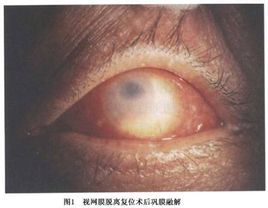

眼眶真菌病病變位於眶前部者,早期可以表現為眼眶蜂窩織炎或栓塞性靜脈炎。眼眶及面頰部脹痛、流涕或鼻出血眼瞼腫脹充血眶內可觸及硬性腫物有壓痛。病變位置較深或眶前部病變向深部發展者眼球突出逐漸加重,眼球呈上或外轉位。眼球運動受限。病變侵及眶尖部時,可出現眶尖綜合徵即視力下降,眼球軸性突出,眼內外肌麻痹,上瞼下垂,面部疼痛。眼底檢查可見視盤水腫,後極部視網膜水腫、視網膜靜脈擴張、視神經萎縮。毛黴菌感染可見鼻腔內有壞死結痂。

病變位置較深或眶前部病變向深部發展者眼球突出逐漸加重,眼球呈上或外轉位。眼球運動受限火罐網。病變侵及眶尖部時,可出現眶尖綜合徵即視力下降,眼球軸性突出,眼內外肌麻痹,上瞼下垂,面部疼痛。眼底檢查可見視盤水腫,後極部視網膜水腫、視網膜靜脈擴張、視神經萎縮。毛黴菌感染可見鼻腔內有壞死結痂健康搜尋。混合細菌感染形成眶膿腫等。

眼眶膿腫可有全身表現,如發熱,畏寒,周身不適。外周血檢查白細胞計數升高,中性核白細胞為主。也可無全身症狀。穿刺抽吸物或在瘺口處取膿液作細菌培養,證實感染細菌屬。眼部見眼瞼充血水腫,瞼裂縮小,結膜充血水腫,嚴重的突出於瞼裂之外,瞼裂不能閉合,結膜乾燥壞死。暴露性角膜炎,角膜潰瘍,前房積膿等。嚴重者眼球突出,眼球運動障礙。由於眶壓增高及眶內靜脈炎,致瞳孔反射消失,視乳頭水腫,視乳頭視神經炎,視力下降甚至黑朦。